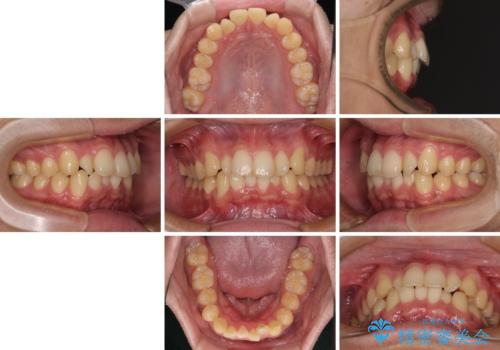

- 上下前歯の捻れやデコボコを気にして来院された患者様です。

マウスピース矯正でもワイヤー矯正でも対応可能でしたが、極力楽をして治したいとのことでワイヤー装置にて治療をおこなうこととしました。

口元はそれほど突出しておらず、患者様自身も気にしていらっしゃいませんでしたが、前歯の捻れやデコボコを解消すると、前方に拡大され、治療後に出っ歯仕上がりとなるリスクがあったため、補助装置により上顎臼歯を後方移動していくこととしました。